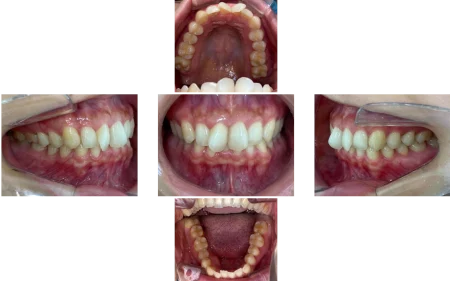

拝見したところ、上左右の前歯(中切歯/1番)はスペース不足のため歯が捻れて生える「捻転」が見られました。

また、上左右の前歯は横から見た時に少し前に出ている「上顎前突(出っ歯)」の状態でもありました。

下の前歯4本(中切歯、側切歯/2番)は、デコボコに並ぶ「叢生(そうせい)」がやや認められました。

奥歯の噛み合わせは特に問題のない状態でした。